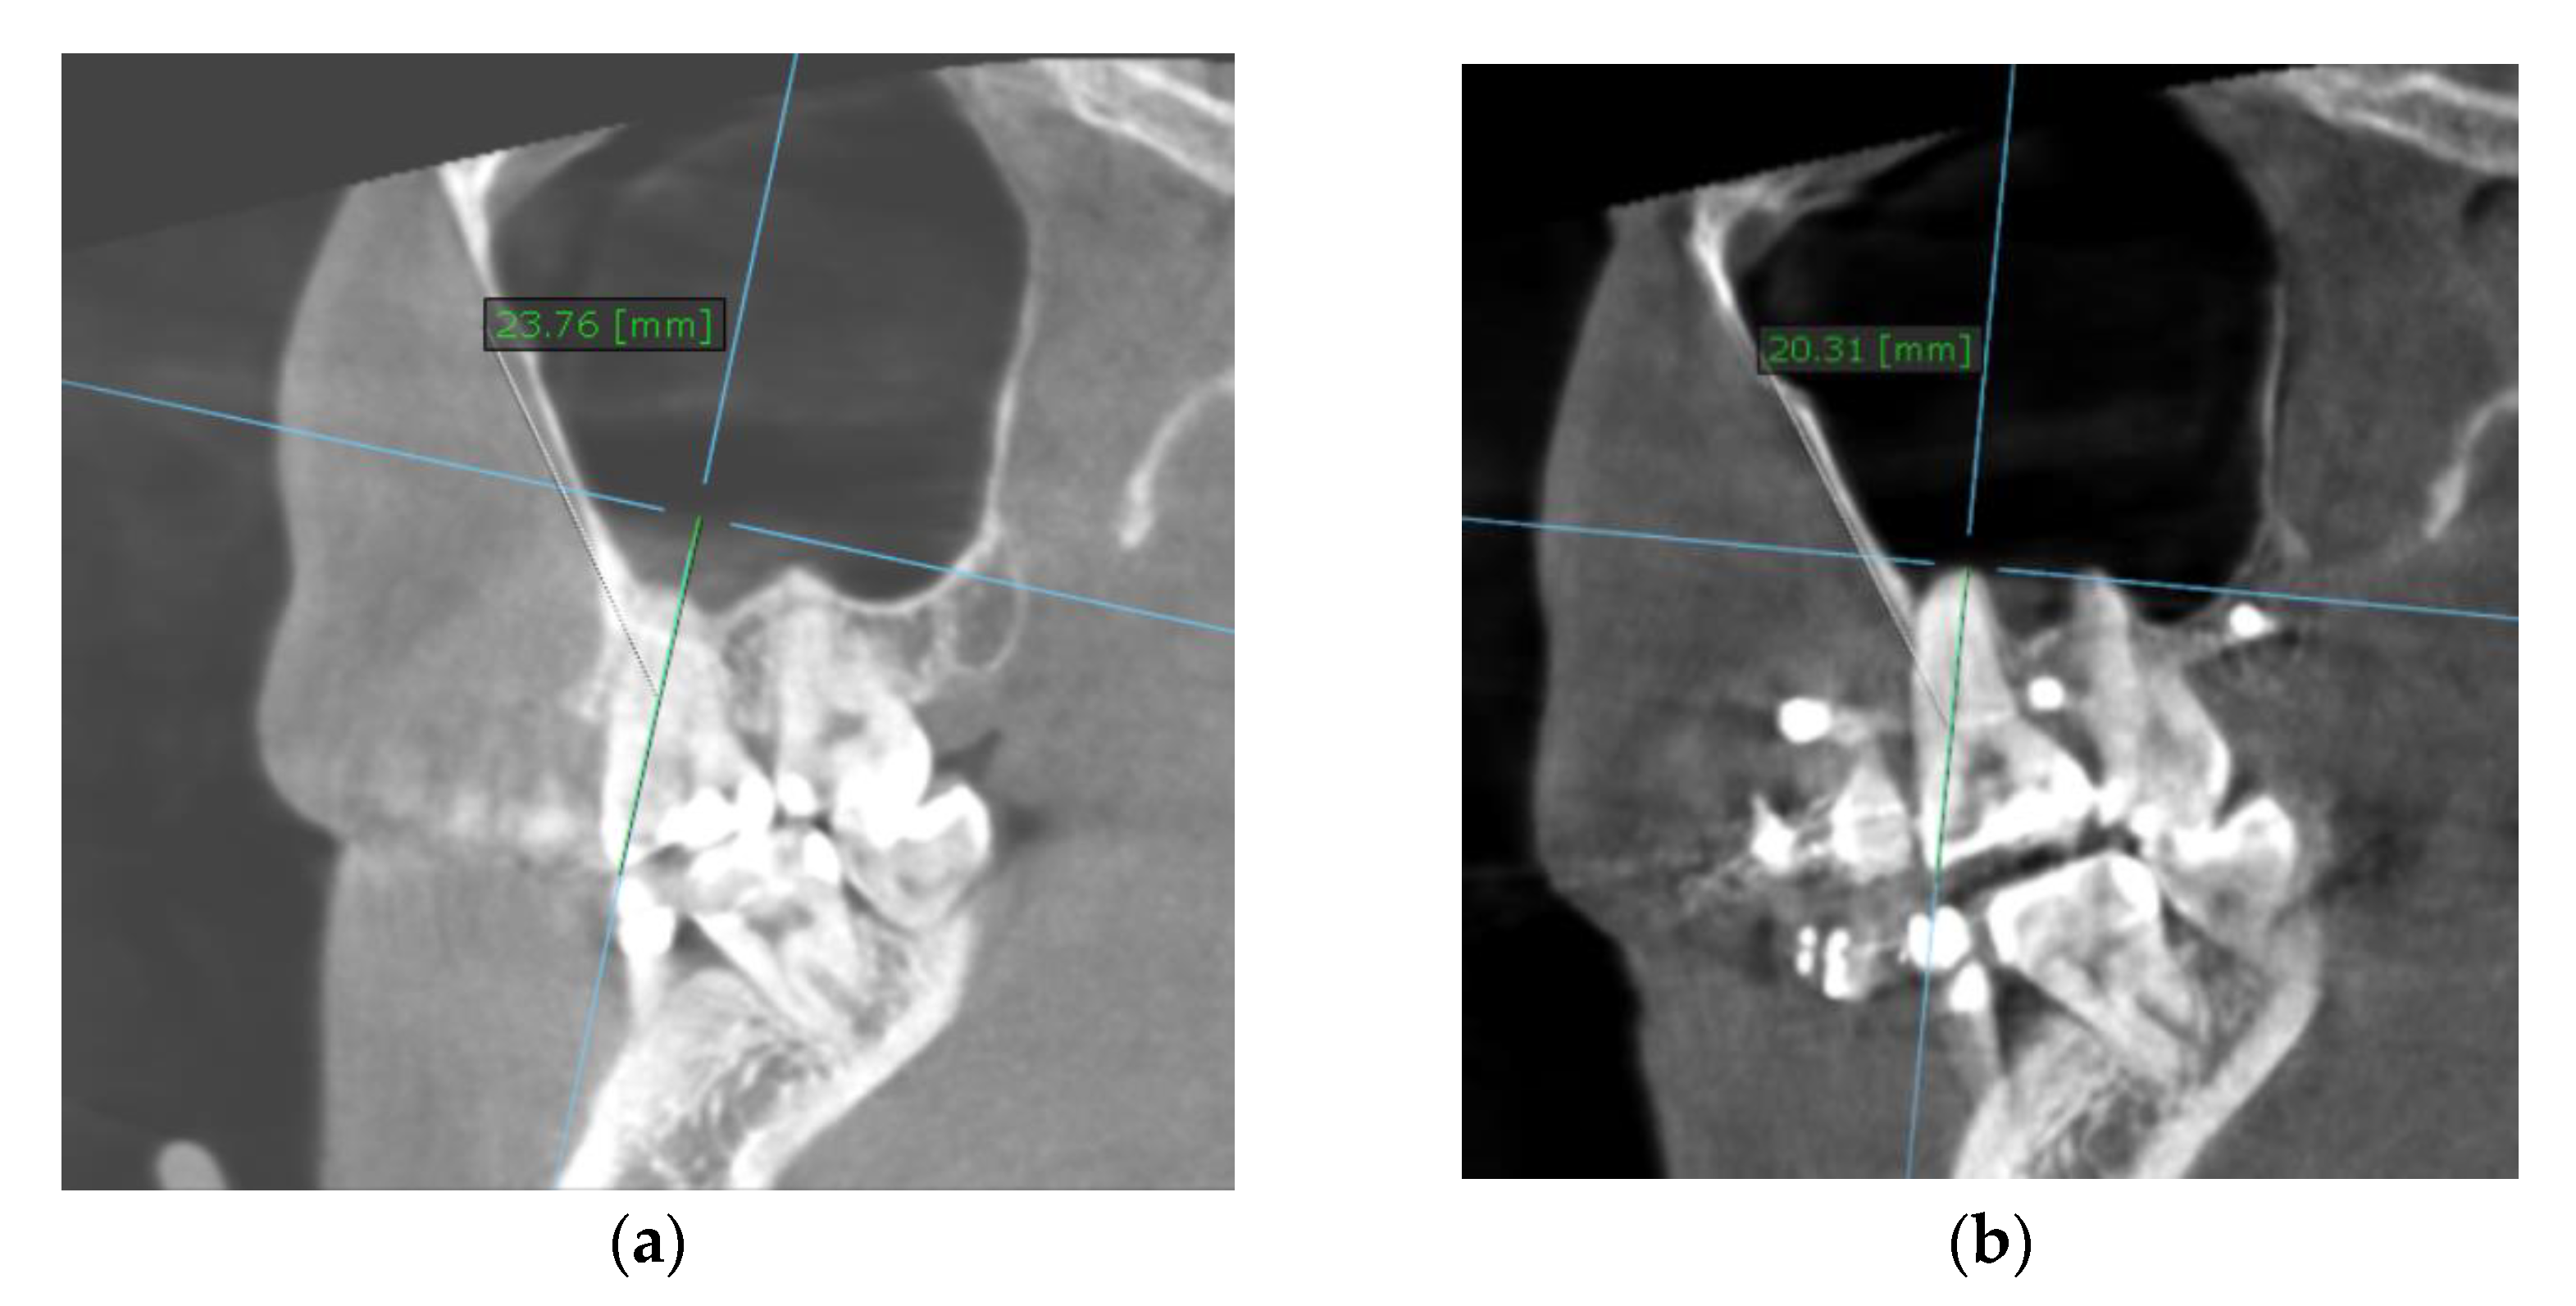

To calculate the amount of performed molar intrusion, the difference of the linear distance from the mesiobuccal cusp of the maxillary first molar to a custom palatal plane (CPP) was measured on CBCT images before and after intrusion mechanics. The CPP was defined by the following three points: ANS, and the lowest points of the pterygoid hamulus on the left and right sides. The measurements were performed by one maxillofacial surgeon and one orthodontist, twice, and mean values were considered (Table 4).

Table 4.

The CBCT measurements before and after intrusion at the level of upper first molar and upper first premolar.

The measurement method is shown in Figure 7.

Figure 7.

Intrusion amount, at the level of the mesiobuccal cusp of the right upper first molar (the distance between the cusp tip and CPP): (a) before intrusion: 23.76 mm; (b) after intrusion: 20.31 mm.

Elastomeric chains were changed every four weeks. Approximately 3.59 mm of intrusion was achieved on the right buccal side and 2.21 mm on the right palatal side in six months, 2.26 mm on the left buccal side, and 1.86 mm on the left palatal side in nine months. After intrusion, ligature stainless steel wires were used to keep the intruded teeth in place. Subsequently, upper and lower teeth were included in a full arch appliance, with a 0.022 MBT prescription.

The recommended loading force of the anchorage devices has been suggested to vary between 50–500 g, reported as 50 g [46,47], 100–200 g [48,49], or 300–500 g of force [50]. If intrusion of more than one single tooth is needed at the same time, the force should be higher, around 400 g [51]. The recommended amount of intrusion of the overerupted maxillary molars is approximately 0.5–1.0 mm per month, without the occurrence of unwanted secondary effects, such as root resorption, periodontal effects, or vitality loss [11]. In the reviewed publications, intrusion force varied between 100 and 500 g. The use of skeletal anchorage can aid in an increased amount of molar intrusion, allowing for accelerated orthodontic forces [52]. Nonetheless, we encourage close monitoring to minimize the risk of undesired side effects. In most studies, the amount of intrusion was obtained by measuring the distance between a reference point on the first molar and the palatal plane on lateral cephalograms. Most of the available studies using 3D imaging measure distance from various tooth landmarks to the palatal plane, defined as passing through anterior nasal spine (ANS), posterior nasal spine (PNS), and perpendicular to the mid-sagittal plane [29]. Baek et al., using 2D imaging, defined the plane as crossing through the ANS and PNS [53]. Although this study met most of our inclusion criteria, it was excluded due to the fact that the study protocol included extractions. Although 2D measurements are easier to perform and more reproducible, very few parameters can be evaluated, leaving 3D imaging as the most precise and relevant alternative. Due to the uncertainty of the definition of the mid-sagittal plane, selecting this landmark might be a source of bias since various factors can influence measurements from pre-treatment and post-treatment CBCT scans. This is the reason why, for the present case report, we decided to define a custom plane, that can always be reproduced with maximum accuracy. This plane is defined by ANS and the lowest points of the pterygoid hamulus on the left and right sides.

A strong point of the present study, besides the thorough literature analysis regarding TADs, is the definition of a custom plane that can be used for exact measurements, to evaluate tooth intrusion. The classical PP can be affected by several patient- and device-specific factors, rendering the pre- and post-operative measurements ineffective. Measuring the distance from certain tooth landmarks to the CPP will always yield useful and relevant findings, since this plane is defined by anatomical landmarks that can not suffer changes throughout tooth ingression.